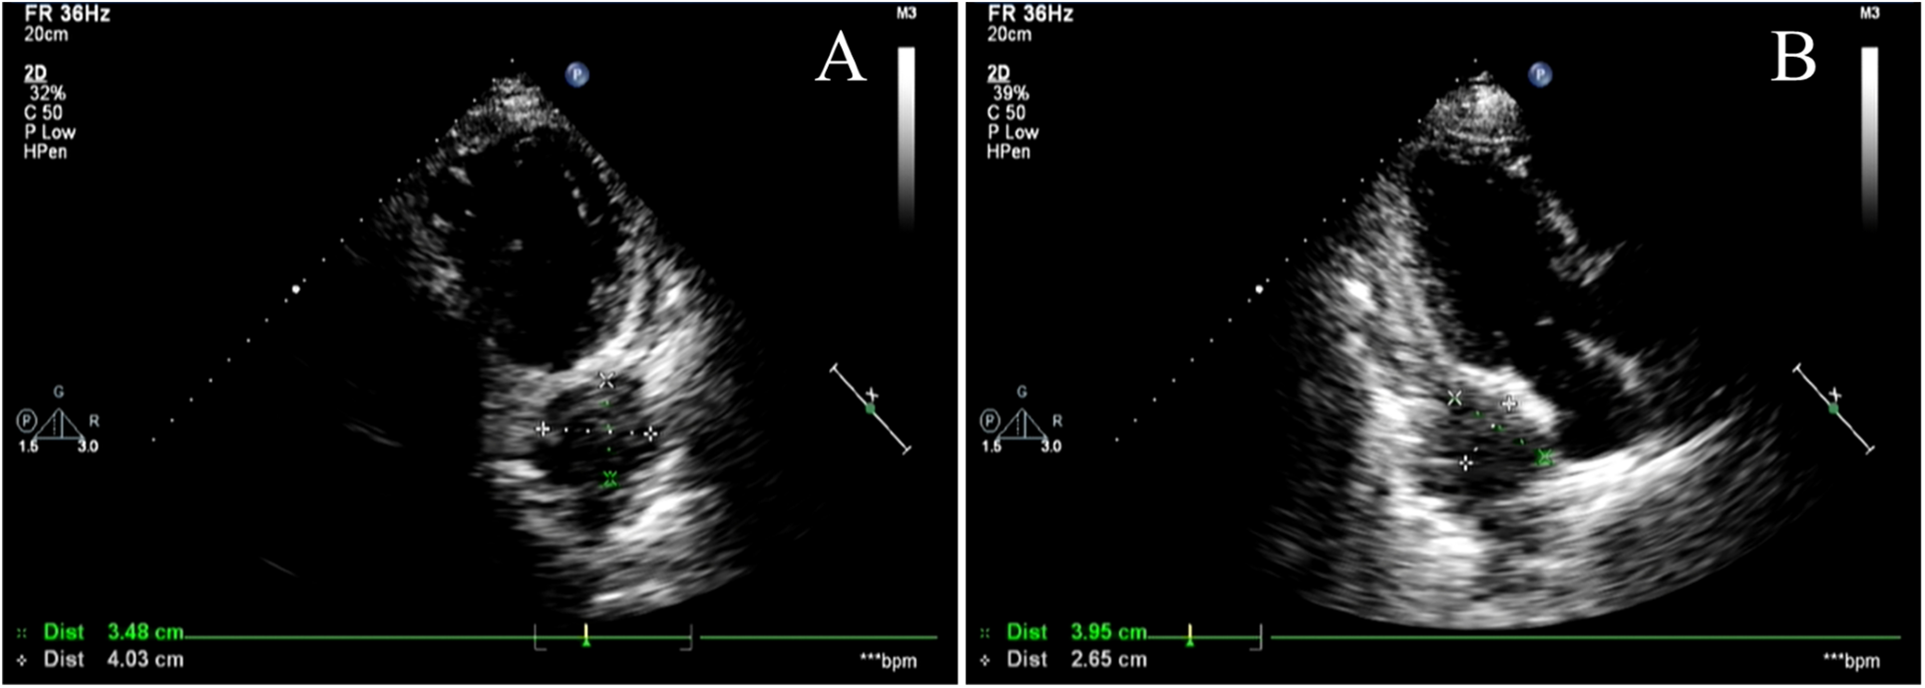

The patient's electrocardiogram was perfected on August 28, 2024 (see Figure 3), and compared with the ECG from July 15, 2024 (see Figure 4), changes in ST-segment elevation were observed in leads I, II, aVL, aVF, and V2–V5. Combined with the patient's symptoms, signs, elevated ultrasensitive troponin, and other indicators, an acute myocardial infarction was diagnosed. A coronary angiography was performed on August 28, 2024. No stenosis was seen in the left main stem (LM), the proximal stenosis in the left anterior descending branch (LAD) was about 60%, and no significant stenosis was seen in the left circumflex branch (LCX) or the right coronary artery (RCA). Coronary angiography results (see Figure 5). Combined with the results of coronary angiography, the diagnosis of acute myocardial infarction could be excluded. Medically, symptomatic treatments such as antiplatelet aggregation and lipid-lowering were given. During hospitalization, a cardiac ultrasound revealed a small amount of pericardial effusion (5 mm at the posterior left ventricular wall and 7 mm at the lateral wall) and limited abnormal echogenicity in the posterior lateral aspect of the left atrium. This area measured approximately 40 by 35 mm, was slightly hypoechoic, and the nature of the echogenicity was undetermined. Metastasis was not excluded based on the patient's history (see Figure 6). The patient continued with the ninth cycle of BEV + FOLFIRI chemotherapy on September 2, 2024, during which they experienced discomfort including coughing and shortness of breath. On October 5, 2024, they were readmitted due to worsening symptoms. The patient's condition deteriorated, and he elected to discontinue active treatment. He subsequently died. The patient did not undergo pulmonary angiography, cardiac tissue biopsy, autopsy, or histopathological diagnosis. The final clinical diagnosis was: malignant tumor of the umbilical urachal carcinoma, intestinal-type adenocarcinoma (stage IV, with metastases to the lungs, adrenal glands, pericardium, and lymph nodes), and secondary malignant tumor of the pericardium.

Figure 6

Cardiac Doppler ultrasound. (A,B) show different views of cardiac color Doppler ultrasound revealing a localized hyperechoic lesion measuring approximately 40 × 35 mm in the posterolateral region of the left atrium, exhibiting mild hypoechoic characteristics. Metastatic lesions cannot be excluded.